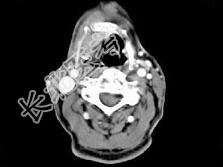

- 单项选择题男,63岁, 咽喉部不适约1年,近两个月经常咳嗽, 痰中带有血丝,CT如图所示, 最可能的诊断是 ( )

A、梨状窝癌

B、声门型喉癌

C、声门下型喉癌

D、声门上型喉癌

E、混合型喉癌